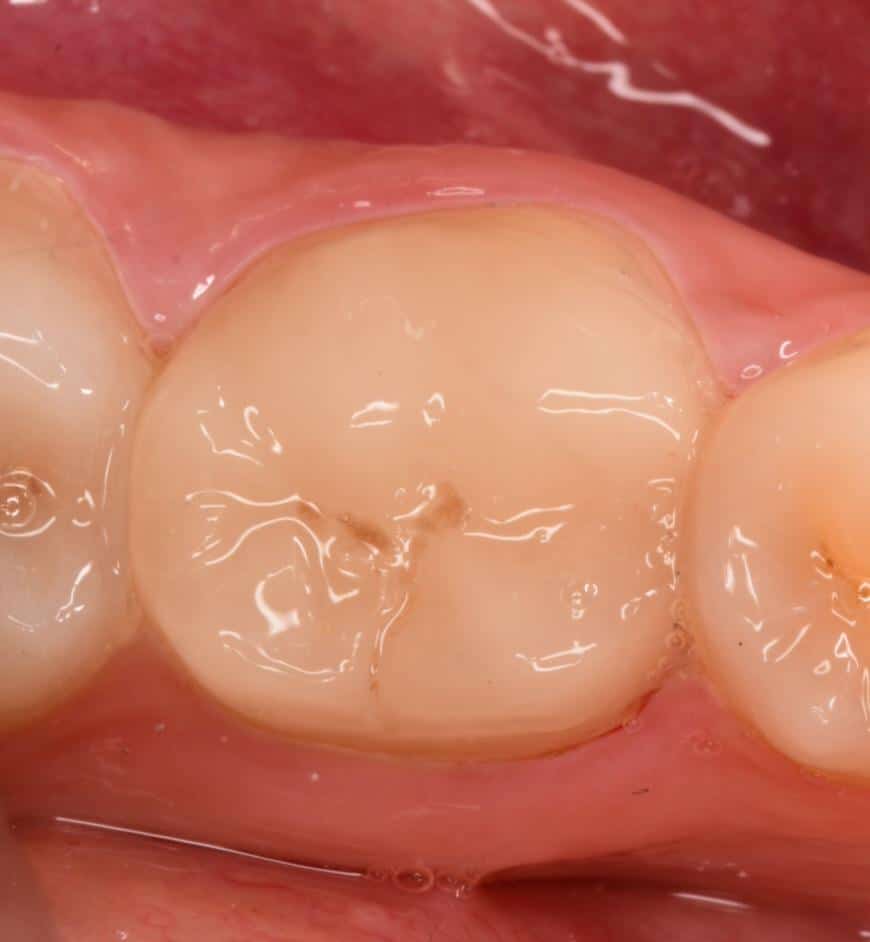

7 months follow-up

2 years follow-up